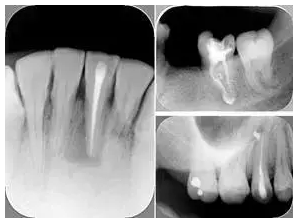

6. 術(shù)后 X 線片

術(shù)后 X 線片用來評定根管充填 長度、致密度(管壁清晰、側(cè)枝)等指標(biāo)。

左圖為根管充填術(shù)后 X 線片。圖中可見,根管充填較好。右下圖有白色小點(diǎn),為側(cè)方加壓導(dǎo)致糊劑擠出所致,表明根管充填比較致密。

致密、恰到好處的充填可去除干凈根管里感染灶,機(jī)體逐漸恢復(fù)。

多根牙時候需進(jìn)行偏移投照,正位投照無法說明具體哪根牙根管充填效果。 二、根管預(yù)備及充填要求